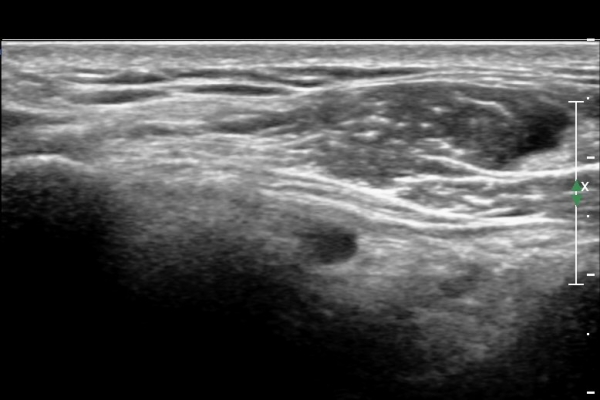

ÃÊÀ½ÆÄ °Ë»ç

¿À±¸µ¹±â°ßºÀÀδë Á¾´Ü¸é°Ë»ç¿¡¼­ ÀÎ´ë ½ÉÃþ¿¡ ¼ö¾×Àú·ù°¡ °üÂûµÊ(»çÁø 1, 2)

ÀÌ´Â Ãæµ¹ÁõÈıºÀ» ¾Ï½ÃÇÏ´Â ¼Ò°ßÀÓ.

°ßºÀÈ¸Ãø Ãæµ¹ÁõÈıº°Ë»ç(°íÂû »çÁø Âü°í)¿¡¼­ °ßºÀ¿ÜÃø¿¡ ¼ö¾×ÀÌ Àú·ùµÇ°í °Ë»ç ½Ã

°ßºÀ ¾Æ·¡¿¡¼­ ÀâÀ½(crepitus)ÀÌ ´À²¸Áü.(»çÁø 6).